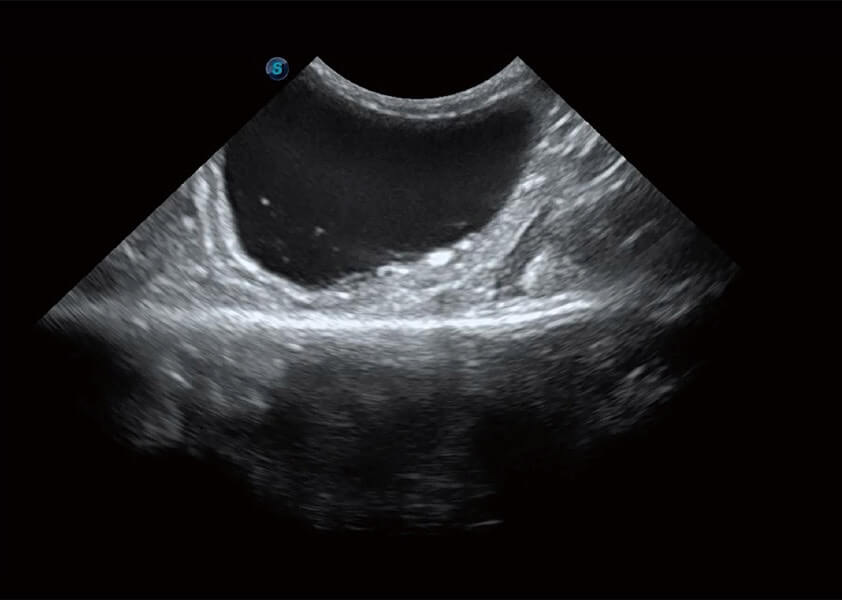

ProPet 60 作为一款高端台式动物超声设备,为动物医生的日常诊断提供了一系列贴合动物临床需求、解决临床实际问题的高级成像功能。凭借全系列高清探头,满足医生对腹部、心脏、生殖、浅表、肌骨等成像的所有需求,切实帮助您提升检查效率,提高诊断信心。

动物是人类最亲密的朋友和最值得信赖的伙伴。环球UG官网也一直致力于探索动物专用的超声影像解决方案。 全新推出的ProPet系列,是环球UG官网在动物超声影像智能化、专业化、精准化的一次跨越式革新。动物不能用言语来表述自己的不适,通过超声影像,ProPet系列搭建了动物医生与不同物种沟通的“桥梁”,为动物医生注入了“治愈之力”。